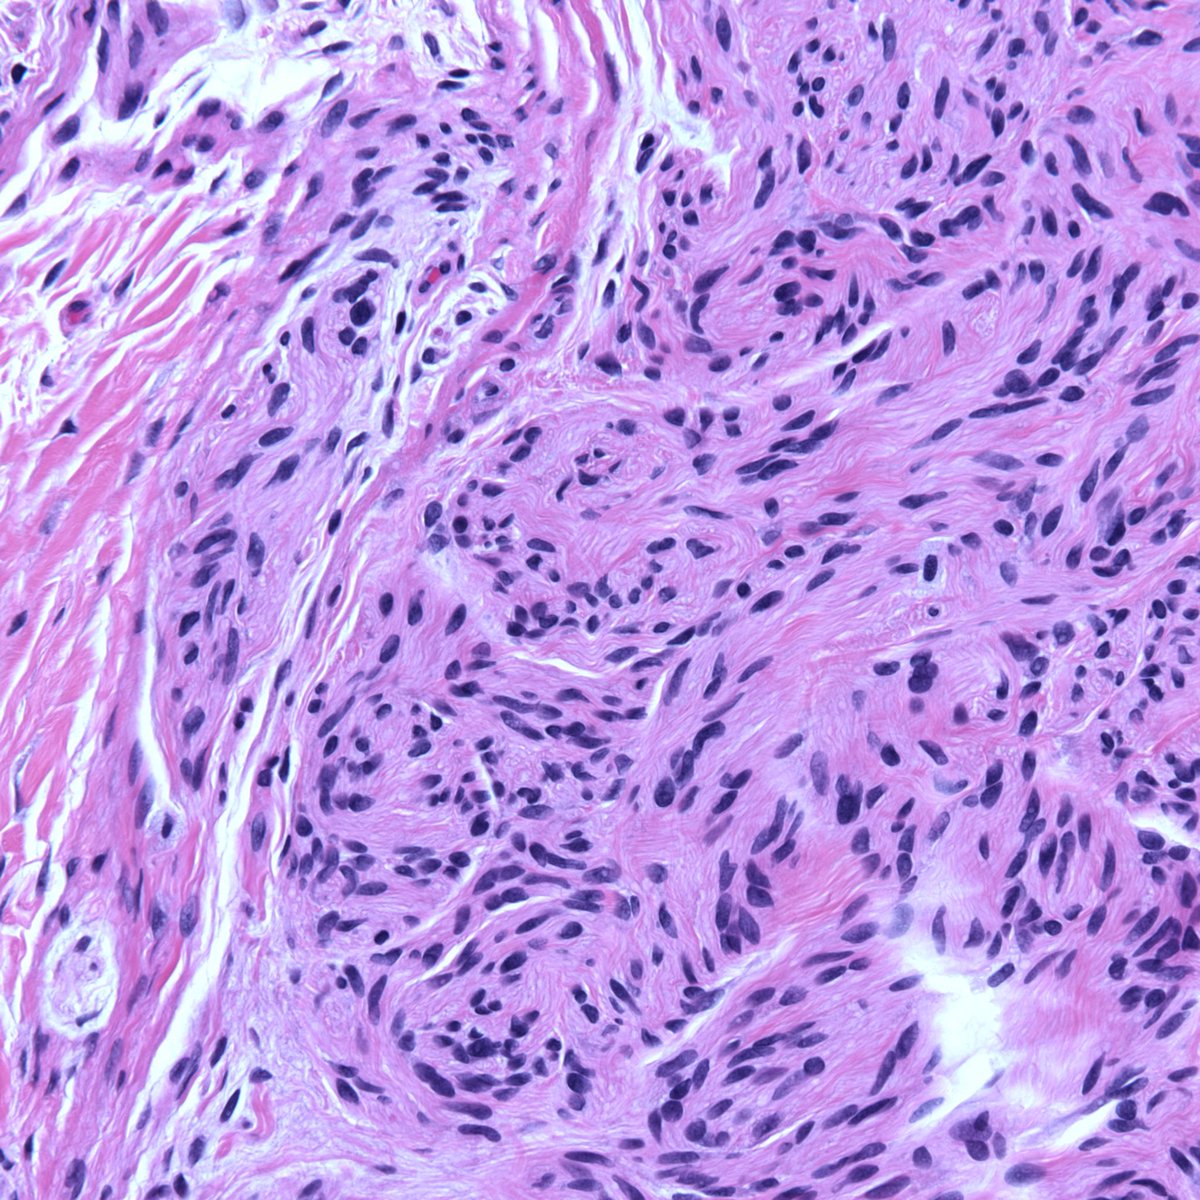

A rare sarcoma worthy of sharing. Sclerosing epithelioid fibrosarcoma. MUC4 IHC shown. First described by my mentor Dr. Meis in 1995. Her more recent study of 51 cases emphasizes its potential for aggressive behavior ➡️ journals.lww.com/ajsp/Fulltext/… #BSTpath #sarcoma

A rare sarcoma worthy of sharing.

Sclerosing epithelioid fibrosarcoma.

MUC4 IHC shown.

First described by my mentor Dr. Meis in 1995. Her more recent study of 51 cases emphasizes its potential for aggressive behavior ➡️ journals.lww.com/ajsp/Fulltext/…

#BSTpath #sarcoma